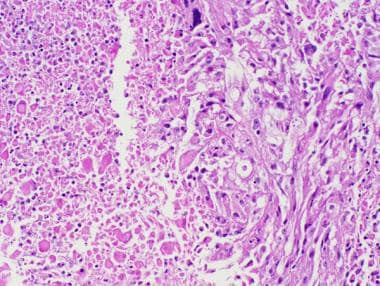

多形性黄色星形细胞瘤可能在诊断时或多年随访后显示坏死区域,这一特征被国际卫生组织(世卫组织)认为符合“具有间变性特征的多形性黄色星形细胞瘤”的诊断标准(苏木精和曙红,20倍原始放大倍数。)